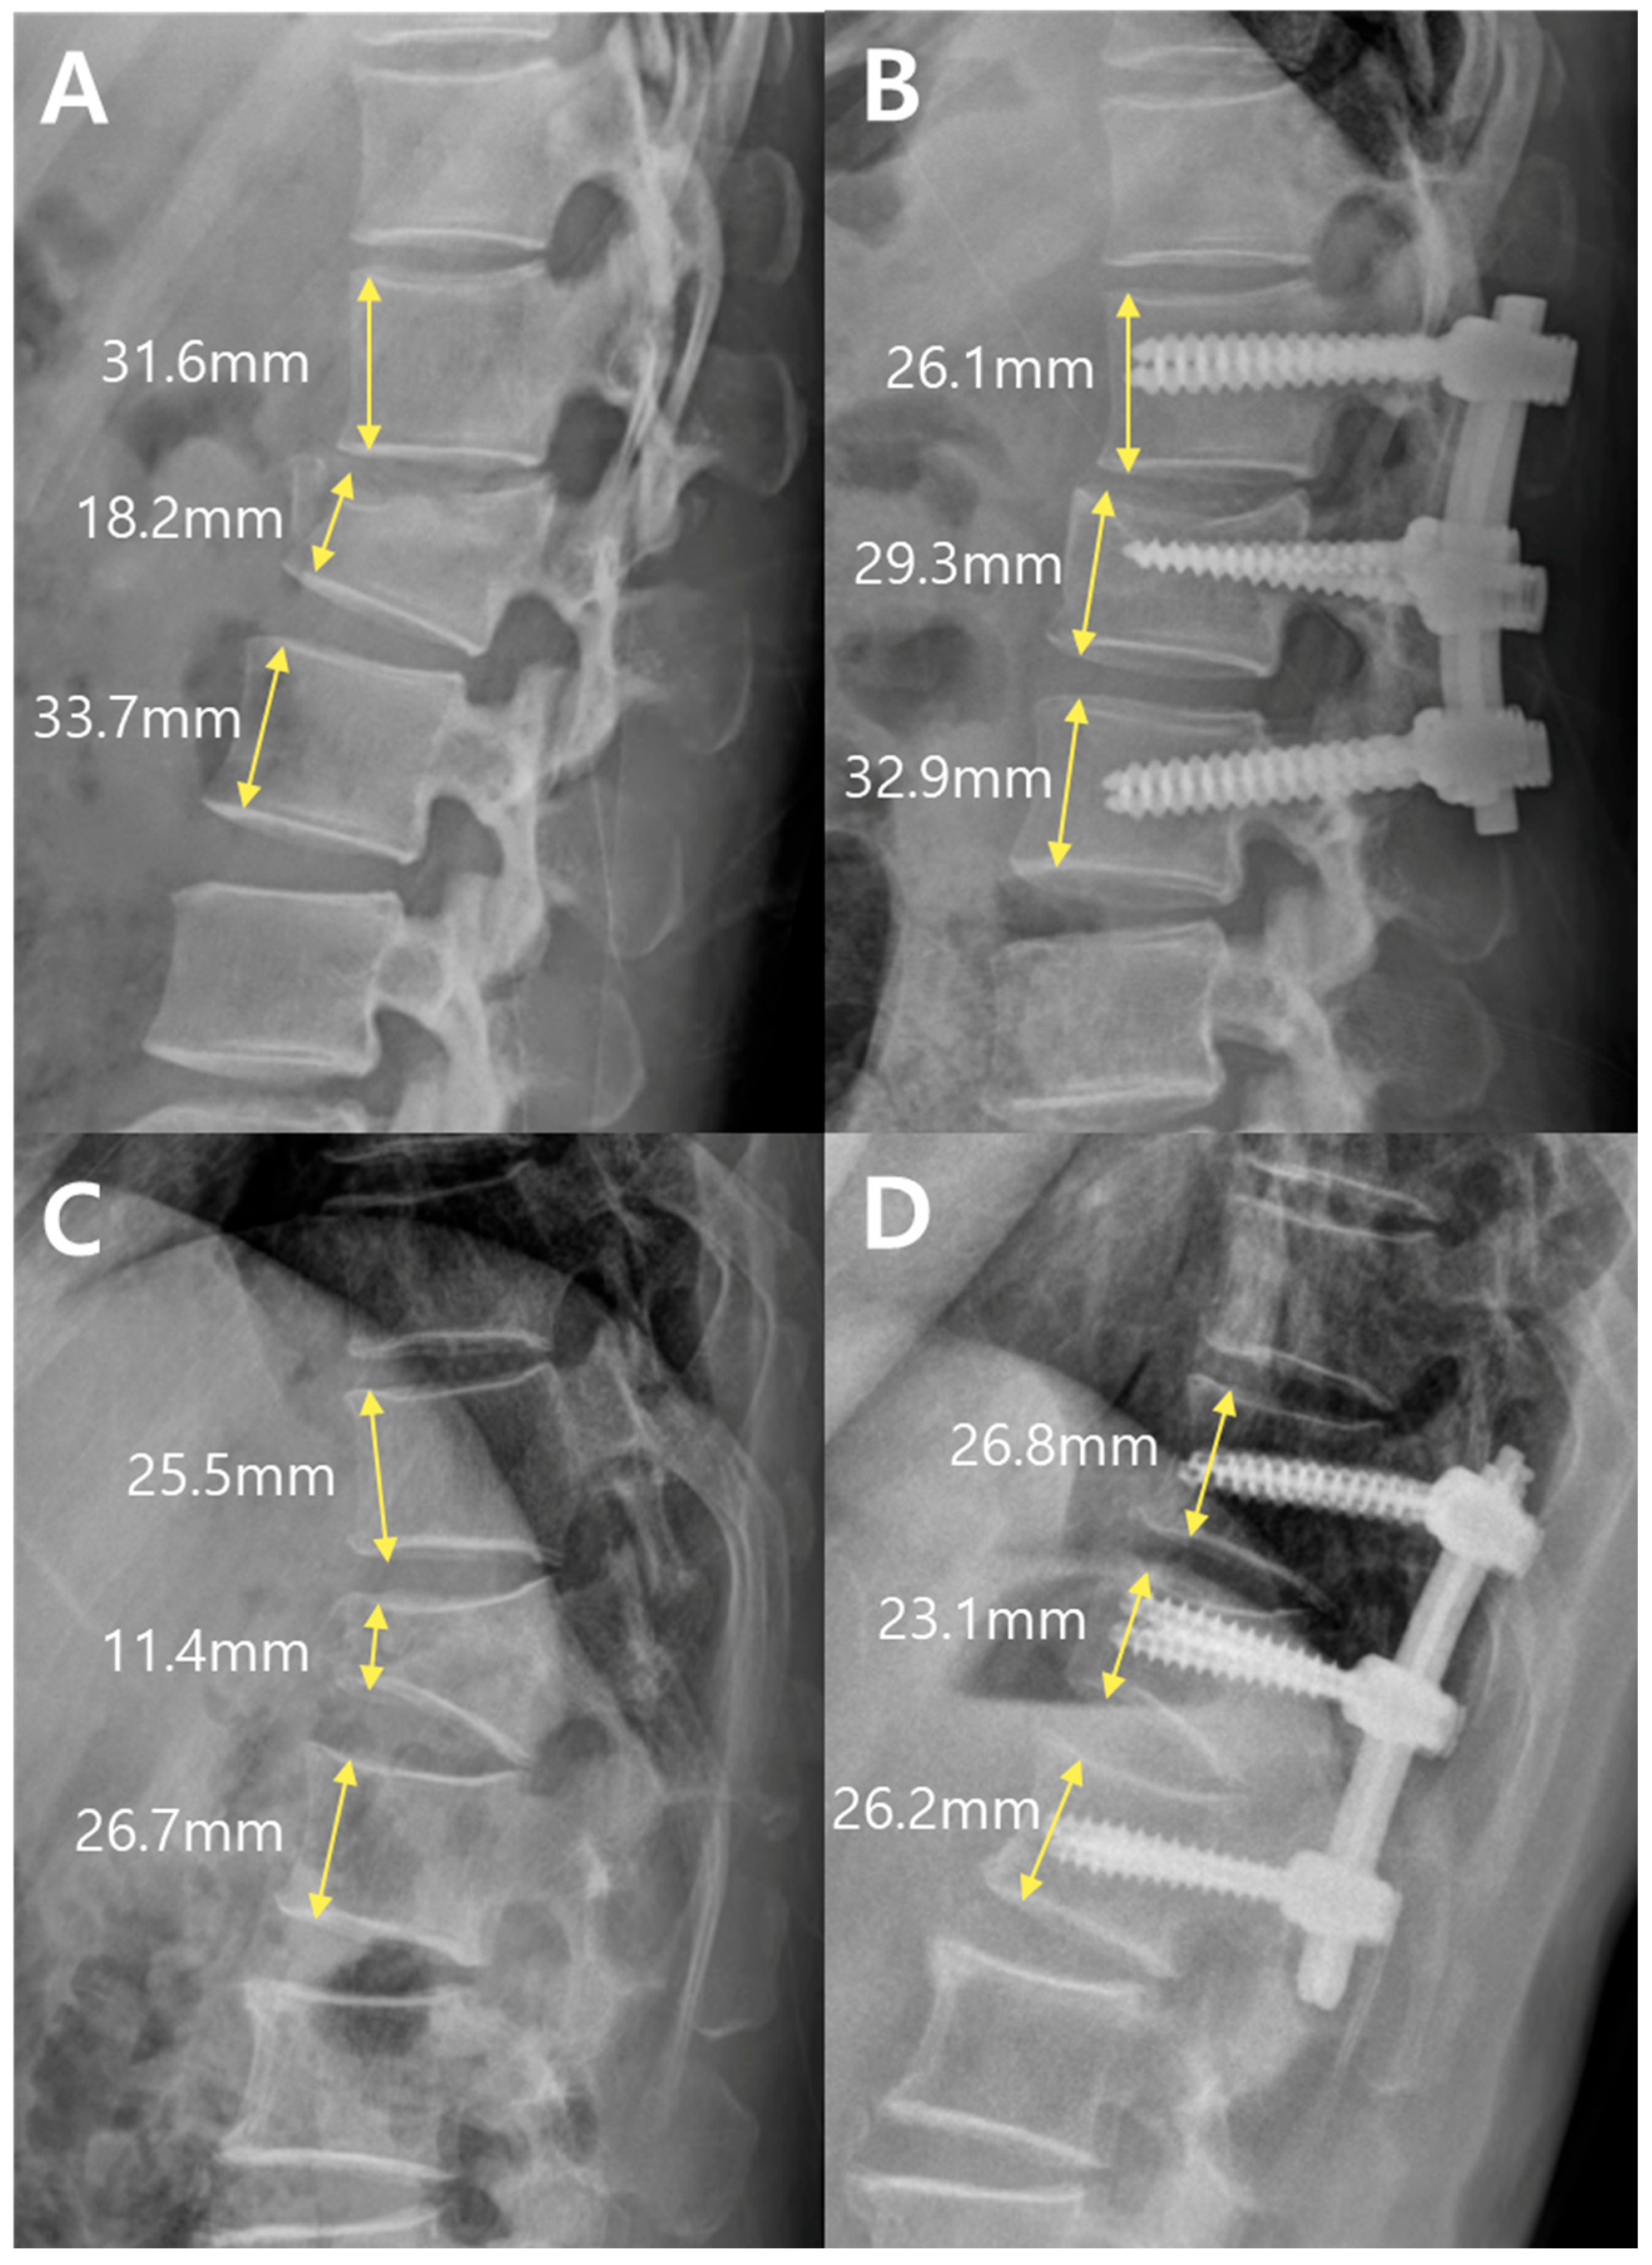

Representative preoperative and postoperative radiographs of both groups are shown in Figure 6. These images visually demonstrate the anterior vertebral height restoration and screw construct placement. Notably, a substantial height recovery was observed even in the absence of bone grafting in the PPF case (D vs. C), highlighting the capacity of percutaneous fixation alone to support vertebral remodeling.

Figure 6. Representative patients from the PLF group (A,B) and the PPF group (C,D). (A,B) Preoperative (Pre) lateral radiograph from the PLF group showing an anterior body height ratio of 56%, and a postoperative (Post) radiograph showing an increased ratio of 99%. (C,D) Preoperative lateral radiograph from the PPF group showing an anterior body height ratio of 43%, and a postoperative radiograph showing an increased ratio of 87%.